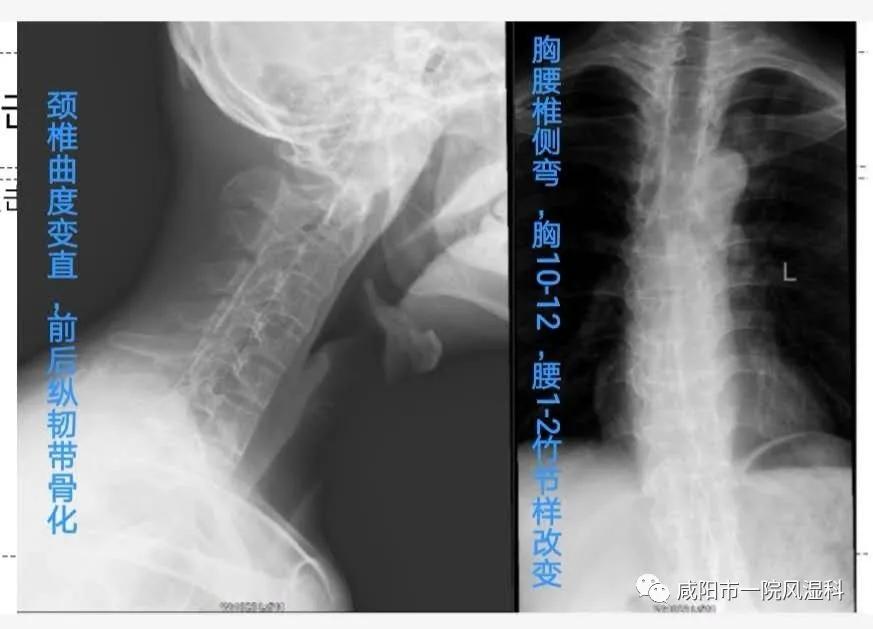

②椎体X线:腰、胸、颈椎受累。

③6年前,我二十七八,我明显驼背了,我的胸椎侧弯了。医生建议我使用生物制剂,可是它又贵副反应又大,我才不上当呢……(第三阶段)

④就在1周前,我连脖子也不能动了,怕啥来啥,这该死的"强直"发展到了颈部……(第四阶段)